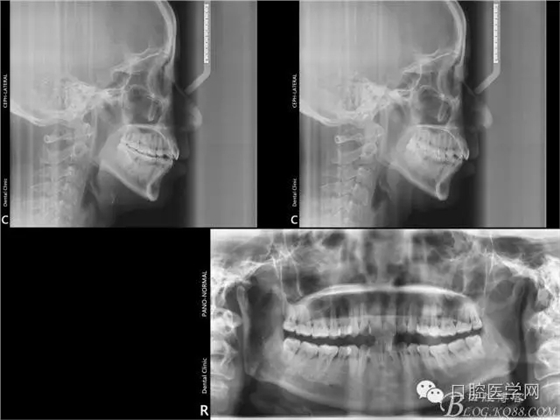

初診照片